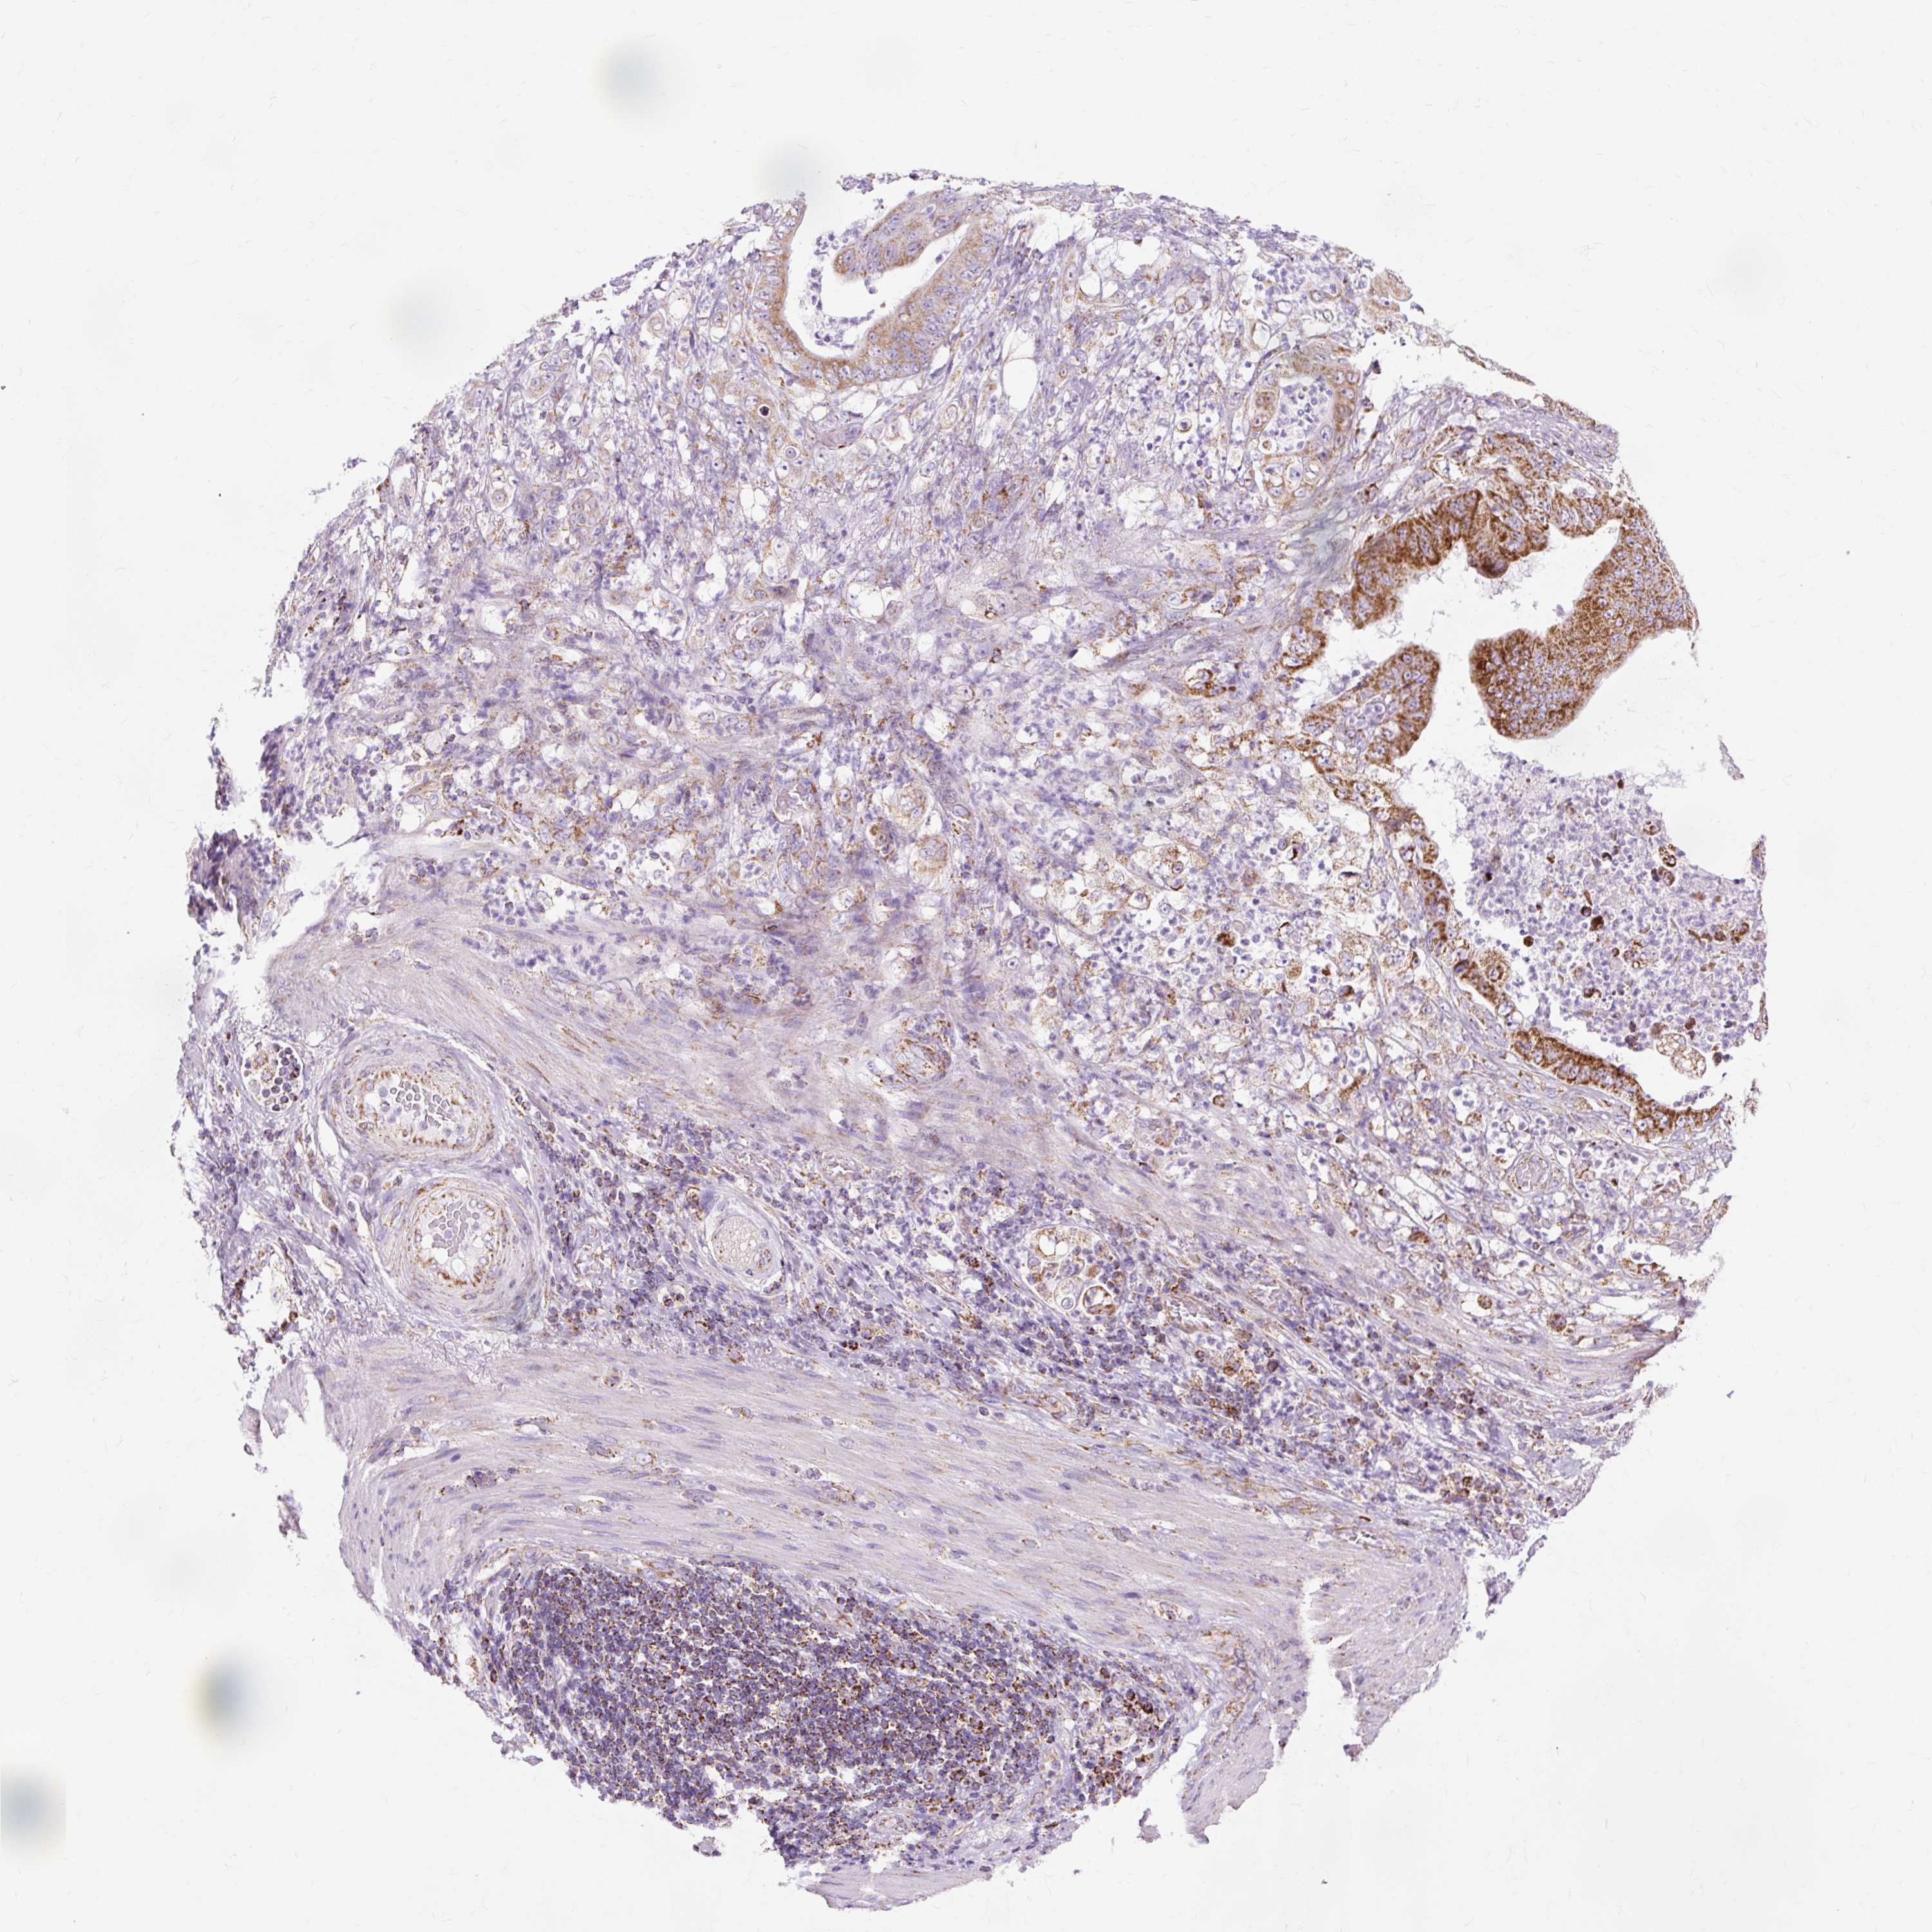

STOMACH CANCER - Protein expressioni

A mouse-over function shows sample information and annotation data. Click on an image to view it in a full screen mode. Samples can be filtered based on level of antibody staining by selecting one or several of the following categories: high, medium, low and not detected. The assay and annotation is described here.

Note that samples used for immunohistochemistry by the Human Protein Atlas do not correspond to samples in the TCGA dataset.

Antibody stainingi

Antibody staining in the annotated cell types in the current human tissue is reported as not detected, low, medium, or high, based on conventional immunohistochemistry profiling in selected tissues. This score is based on the combination of the staining intensity and fraction of stained cells.

Each image is clickable and will lead to virtual microscopy that enables deeper exploration of all samples and also displays staining intensity scores, fraction scores and subcellular localization as well as patient and tissue information for each sample.

Antibody HPA040786

Antibody CAB003782

Staining

High

Medium

Low

Not detected

Intensity

Strong

Moderate

Weak

Negative

Quantity

>75%

75%-25%

<25%

None

Location

Nuclear

Cytoplasmic/membranous

Cytoplasmic/membranous,nuclear

Adenocarcinoma, NOS